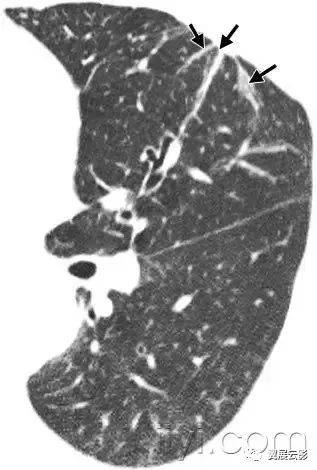

十八、小叶中心性:

解剖:小叶中心性用于描述次级肺小叶的支气管血管束中心区域。病理学上也用这一术语描述终末小支气管远端,位于呼吸性细支气管和肺泡管中心的病变。

CT:正常次级肺小叶中心的点状或者线状的密度增高影,胸膜下25px范围内最明显,代表小叶内的动脉,直径约1mm。

小叶中心性异常包括(1)结节(2)树芽征,提示小气道病变(3)由于临近间质的增厚或者浸润导致小叶中心结果更加清晰(4)小叶中心性肺气肿导致的异常低密度。

附图为小叶中心性肺气肿